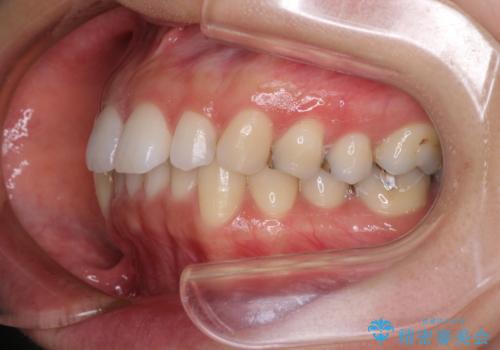

顎先に梅干し皺ができる 閉じにくい唇を抜歯矯正で閉じやすく

- 口元の突出感と口の閉じにくさを気にして来院された患者様です。

上下左右第一小臼歯4本を抜歯し、ワイヤー装置にて口元を引っ込めるよう矯正治療を行うこととしました。

奥歯が前方に傾斜していることで深く咬みこむ(ディープバイト)状態であったので、なかなか抜歯したスペースが閉じず、様々な方法でディープバイトを改善しながら治療を進めていくこととなりました。